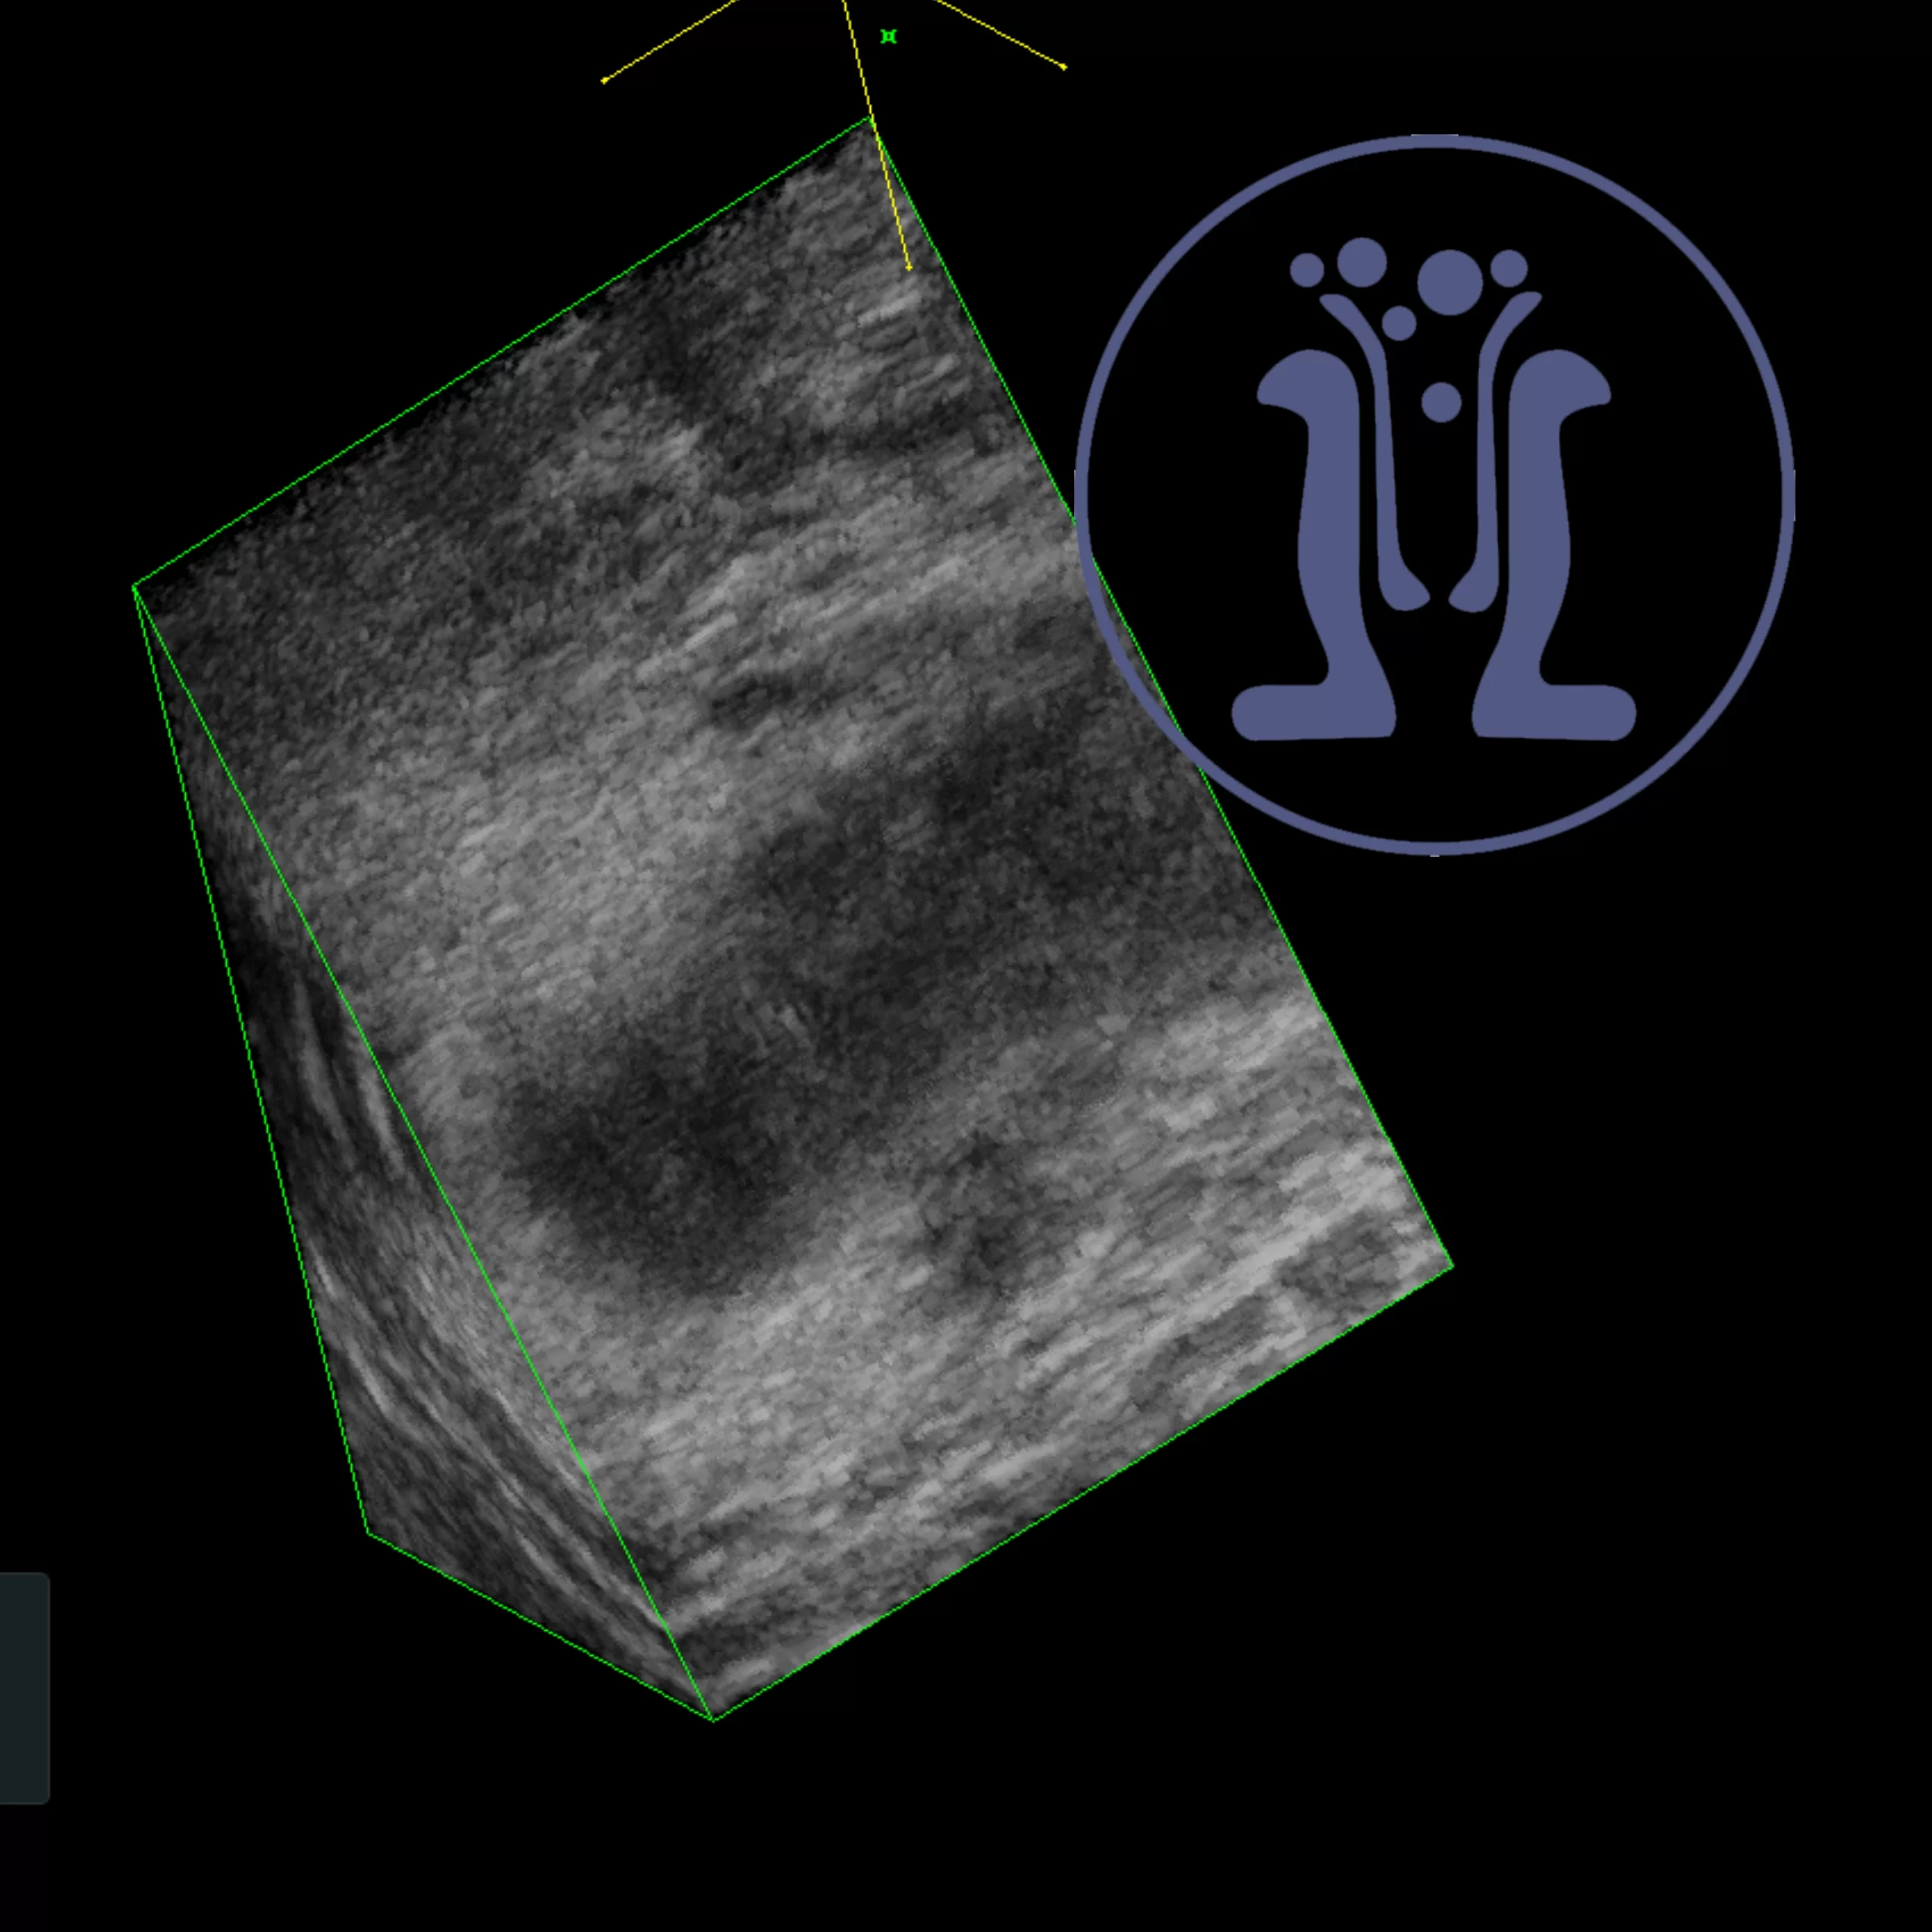

Αυτή την εβδομάδα συναντήσαμε το πέμπτο περιστατικά της διετίας με έντονο πόνο στον πρωκτό που προκλήθηκε από φυτικούς σπόρους. Αυτή την φορά ο ένοχος ήταν ο λιναρόσπορος…Αφαιρέθηκε ο λιναρόσπορος αλλά τελικά χρειάσθηκε επιπλέον χειρουργικός καθαρισμός..